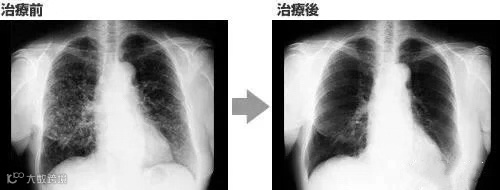

案例3

一名广泛期小细胞肺癌患者,在进行4个疗程化疗和4次高度活化NK细胞回输后,患者第一次进行治疗后的CT复查,结果显示,肿瘤缩小到了原来的1/8。而且距发病第六年的CT复查中,仍旧没有发现任何异常及复发的迹象。